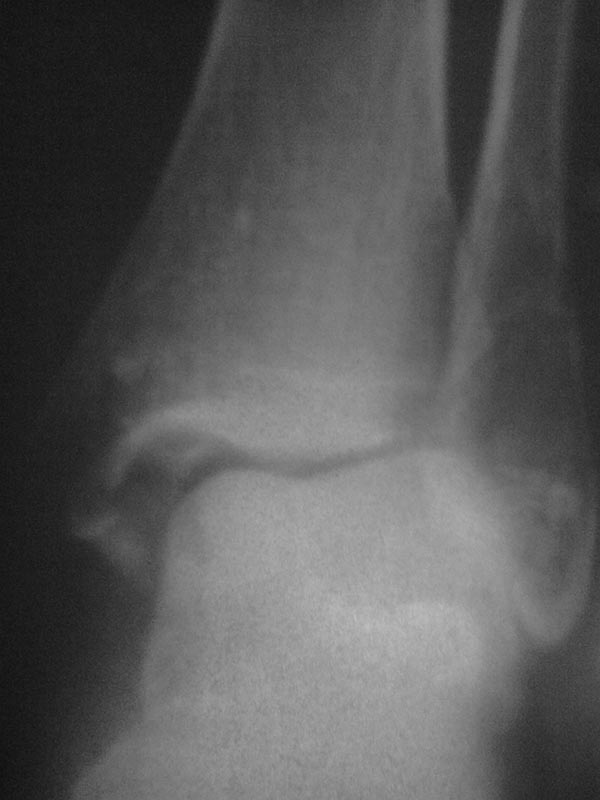

перелом лодыжки

1 февраля был перелом обеих лодыжек. 5 марта гипс сняли.

после снятия прошел месяц . так как я плохо хожу врач пересмотрел снимки и сделал вывод что остался подвывих.и больще ни каких коментариев. кроме как назначили магнит. вот у меня вопрос - не нужна ли операция или возможно все таки лечение и востановление.